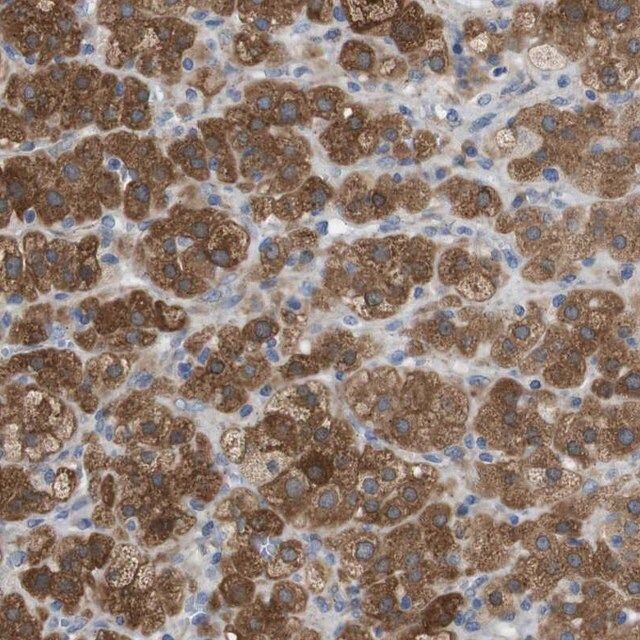

人类蛋白质图谱项目可细分为三个方面的工作:人类组织图谱、癌症图谱和人类细胞图谱。支持 Tissue and Cancer Atlas 项目而产生的抗体,已经通过免疫组化针对数百个正常和疾病组织进行了测试,通过 Human Cell Atlas 项目最近的努力,很多已经通过免疫荧光法进行了表征,不仅在组织级别,现在也在亚细胞级别绘制了人类蛋白质组图谱。通过点击图像库链接,可以在 Human Protein Atlas (HPA) 位点上查看这些图像和这个庞大数据集的集合。要查看这些协议 和其他有关 Prestige 抗体和 HPA 的有用信息,请访问sigma.com/prestige。

- 44例正常人类组织以及20例最常见癌症类型组织的IHC组织阵列。